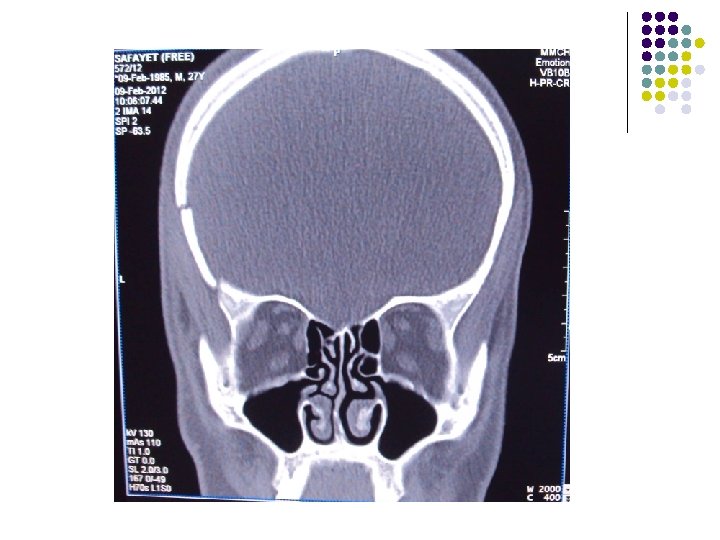

CT Scan of Brain

Clinical Diagnosis Retrobulbar solid tumour on left orbit